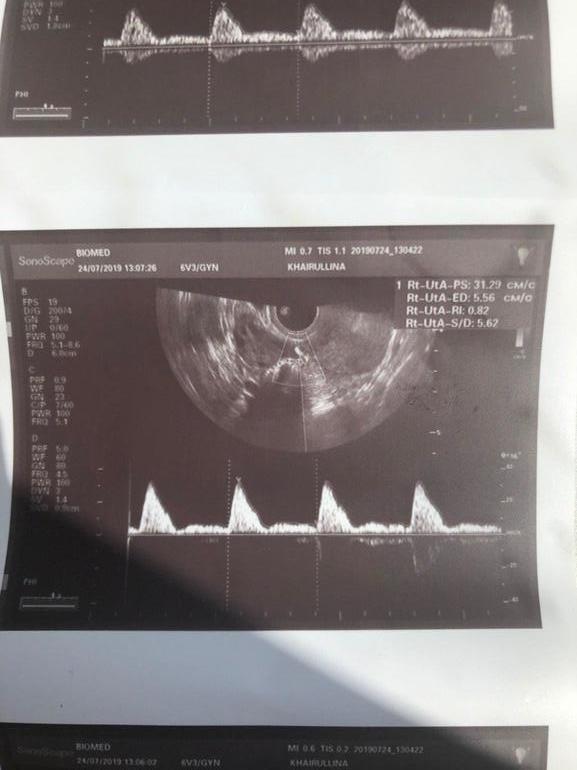

сегодня у другого врача в другой клинике 7,8......(((ну и сам доплер, помогите пожалуйста, разобраться , узист делала молча, в заключении ничего нет

1.Правая маточная артерия 2.Левая маточная артерия 3.Аркуатные артерии 4.Радиальные артерии 5.Базальные артерии 6.Спиральные артерии Наиболее важные для имплантации и вынашивания на первоначальном этапе и наиболее часто страдающие от ХЭ артерии - это Базальные и Спиральные. Пока кровотока в них нет, или он снижен, беременность может продолжать срываться/замирать. Правая и левая маточные артерии не столь важны для вынашивания на первоначальном этапе. Однако обычно с ними как раз у большинства все в порядке. Во время измерения сосудов, на экране монитора будут ловить пульсацию в каждой артерии, и вы будете видеть примерно такую картинку: УЗИст же будет замерять эту пульсацию. Это правильное исследование. Часто доплером называют еще вот этот "режим цветных пятен": Это тоже кровотоки в режиме доплера. Многие УЗИсты просто смотрят именно этот режим доплера и сообщают вам, что все хорошо. Не ведитесь! Информации о скорости кровотоков такое исследование не несет. Когда делать доплер? Доплер сосудов матки необходимо делать на 5-7 ДПО (день после овуляции). Нормы доплера есть на любой день цикла, и в принципе узнать о плохом кровотоке вы можете, сходив на доплер в любой ДЦ. На 5-7 ДПО его смотрят за тем, что это время приходится на окно имплантации при возможной беременности. Какой нужно получить результат от УЗИста на руки? Правильный результат доплера выглядит как все перечисленные выше артерии с количественными показателями, включая самый популярный - Индекс Резистентности (ИР). (Или только с ИР, этого достаточно). Если по-английски, то RI. Данный индекс характеризует скорость кровотока и имеет свои нормы. Резистентность - это сопротивление, то есть чем ИР ниже, тем лучше, тем быстрее кровоток, а значит лучше для беременности. То есть когда говорят о высокорезистентном кровотоке, имеют ввиду, что кровоток плохой. Соответственно, на руки вам должны выдать результат ИР во всех шести артериях матки и вывод УЗИста о состоянии кровотока. Каковы нормы доплера? Нормы ИР для второй фазы цикла:

1.Правая маточная артерия 0,71-0,90